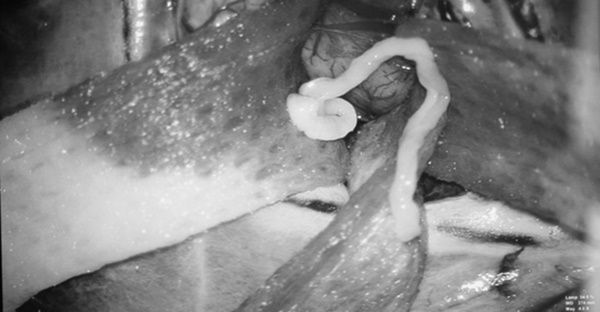

Con sán nhái dài 7 cm chui lên não người đàn ông 52 tuổi - Ảnh: NP.

Trước đó, một bệnh nhân nam 52 tuổi ở Lâm Đồng bị đau đầu, co giật, yếu nửa người đã được các bác sĩ Bệnh viện Đại học Y Dược TP HCM gắp từ não một con sán dài khoảng 7 cm. Giải phẫu con sán sau đó xác định là loài sán ký sinh trong nhái.